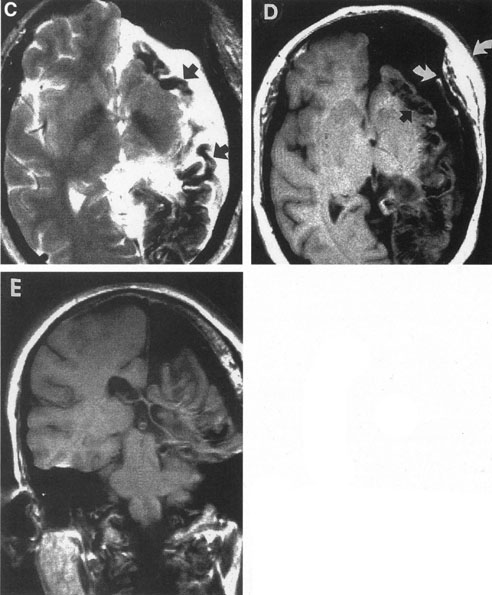

Of particular interest are those AVMs that involve the occipital lobe (Fig. 9). The clinical differentiation of migraine from a cerebral AVM was previously regarded as difficult because the clinical features of occipital lobe AVMs include visual phenomena or headaches. However, in most cases the clinical distinction is possible. In 26 cases with occipital AVM, two distinct syndromes were defined in 18 patients: occipital epilepsy and occipital apoplexy.73 Focal seizures with occipital malformations consist of elementary visual sensations similar to the phenomena evoked by direct cortical stimulations. When seizure activity occurs in the striate cortex (area 17), the patient usually reports sensations of moving lights in the right or left homonymous fields. The sensations are poorly formed, episodic, usually brief, sometimes colored, and unassociated with the angular, scintillating figures so characteristic of migrainous cortical phenomena. Epileptic discharges from areas 18 and 19 cause photopsias that are unlikely to remain stationary and to flicker rapidly. The epileptic photopsias usually last only seconds; occasionally they last for a few minutes before the onset of a generalized seizure. In other instances only the brief visual episodes occur without spreading to produce a generalized seizure. Momentary dimming or blindness in one or both homonymous fields may be experienced with seizure activity in the occipital areas.

Fig. 9. Carotid arteriogram of an occipital lobe arteriovenous malformation (AVM). Lateral (A) and frontal (B) projections demonstrating a small occipital AVM (arrow). The patient was a 23-year-old woman who presented with severe apoplectic unilateral headache, total left homonymous hemianopia, and mild nuchal rigidity. Despite xanthochromic cerebrospinal fluid, she was initially diagnosed elsewhere as having migraine. An AVM was successfully resected, and a small occipital lobe hematoma was removed.

Occipital apoplexy results from hemorrhage and hematoma formation within the occipital lobe and is characterized by sudden severe headache and homonymous visual field loss. Homonymous hemianopia is the most important sign produced by vascular malformations of the occipital lobe. Compression and necrosis of visual pathways by an intracerebral hematoma are the principal mechanisms. Usually the hematoma is large and tends to split or dissect longitudinally through the white matter of the occipital lobe. The effects of compression may be reversed by prompt, surgical evacuation of the hematoma.73 With hemorrhage into one occipital lobe, hemianopia in the visual field of the contralateral normal occipital lobe may develop, producing total blindness that can last for several days. The rapidly expanding hematoma may shift the damaged hemisphere anteriorly, or across the midline, with downward herniation of the uncus through the tentorial incisura. This shift compresses the posterior cerebral arteries and accounts for bilateral occipital lobe dysfunction. Arrest of function in the undamaged occipital lobe may be due to an interhemispheral inhibitory phenomenon termed diaschisis. Visual field defects with occipital AVMs are regularly due to hemorrhage and hematoma formation. Congenital arteriovenous malformations can occupy the entire occipital pole (the macular projection area) for decades without producing visual field defects.

Although migraine is often cited as a symptom of AVM, it is extremely rare that classic migraine is mimicked by occipital AVM. None of the patients in the series by Troost et al73 described the 15- to 20-minute episodes that characterize the visual aura of classic migraine. The headaches of AVM differ from migraine in that they are constantly localized to the same side of the head, and intermittent visual phenomena, if present, can persist throughout the headache or even after, whereas in migraine the visual phenomena usually precede the headache. Bruyn74 has reviewed the clinical features of 57 reported and 7 personal cases of AVM, concluding that the migraine of AVM is late onset, nonfamilial, and brief. Rarely, the complete clinical symptomatology of classic migraine can be mimicked by an occipital lobe AVM (see Chapter 16).75 In addition to hemianopia, other visual disturbances can occur after hemorrhage into the occipital lobe, including alexia without agraphia (see Chapter 7).